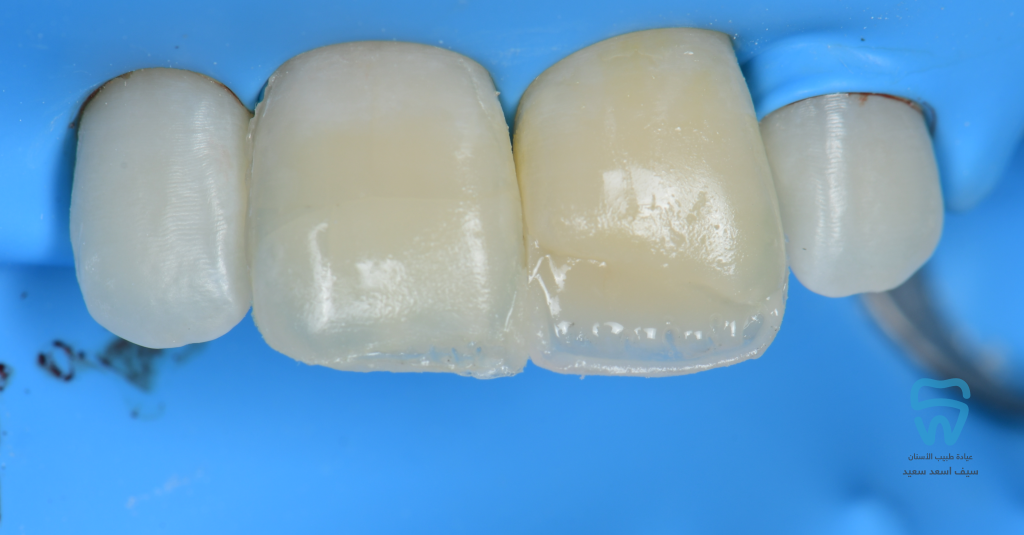

closer look at the condition

The fractured segment of the right central